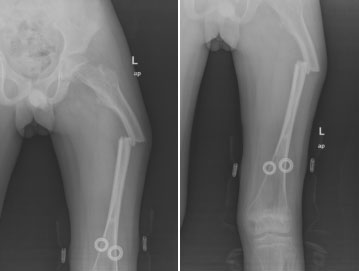

圖為患者股骨弓形變截骨矯形可延長(zhǎng)釘內(nèi)固定術(shù)后影像學(xué)資料

術(shù)后小兒骨科按照術(shù)前制定的護(hù)理及康復(fù)方案,從術(shù)后傷口護(hù)理、體位護(hù)理、下床訓(xùn)練、扶拐行走訓(xùn)練等各方面指導(dǎo)患者進(jìn)行康復(fù)?;颊哂诮谥斡鲈?。這是玉溪市中醫(yī)醫(yī)院獨(dú)立完成的首例兒童成骨不全截骨矯形骨延長(zhǎng)手術(shù),標(biāo)志著我院治療成骨不全邁上了一個(gè)新臺(tái)階。